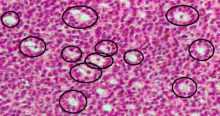

Call–Exner bodies

Call–Exner bodies, giving a follicle-like appearance, are small eosinophilic fluid-filled punched out spaces between granulosa cells.[1] The granulosa cells are usually arranged haphazardly around the space.

They are pathognomonic for granulosa cell tumors.

Histologically, these tumors consists of monotonous islands of granulosa cells with "coffee-bean" nuclei. That same nuclear groove appearance noted in Brenner tumour, an epithelial-stromal ovarian tumor distinguishable by nests of transitional epithelial cells (urothelial) with longitudinal nuclear grooves (coffee bean nuclei) in abundant fibrous stroma.[2][3]

They are composed of membrane-packaged secretion of granulosa cells and have relations to the formation of liquor folliculi which are seen among closely arranged granulosa cells.